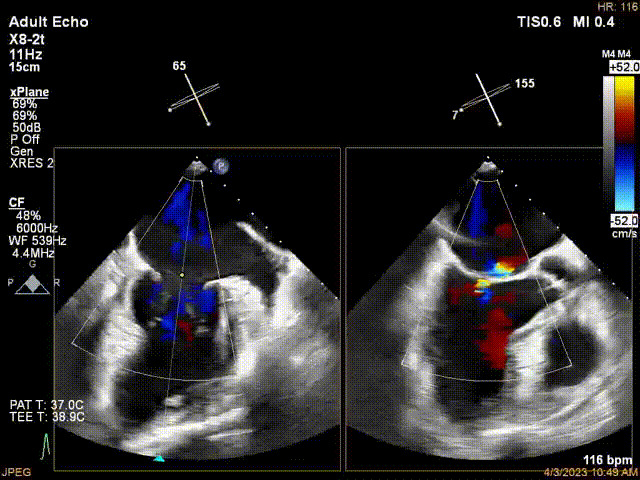

接受治療的是一例器質(zhì)性重度二尖瓣反流(DMR)患者,主訴“反復(fù)活動(dòng)后胸悶,氣促3年余”。術(shù)前超聲顯示,雙房增大,二尖瓣脫垂伴重度反流,輕度三尖瓣反流,輕度肺高壓,升主動(dòng)脈增寬。手術(shù)經(jīng)股靜脈-房間隔入路,采用全身麻醉插管,在TEE和DSA引導(dǎo)下完成房間隔穿刺。置入JensClip瓣膜夾系統(tǒng)后,在左房調(diào)整瓣膜夾的位置和軸向,后進(jìn)入左室,在TEE引導(dǎo)下捕捉二尖瓣前后瓣葉,并關(guān)閉瓣膜夾。經(jīng)TEE反復(fù)確認(rèn)手術(shù)效果后最終鎖定并釋放瓣膜夾。術(shù)后即刻超聲顯示瓣膜夾位置穩(wěn)定,功能良好,術(shù)前二尖瓣反流4+,術(shù)后0反流,肺靜脈逆流和左房壓都顯著好轉(zhuǎn),手術(shù)圓滿(mǎn)成功(以上數(shù)據(jù)都來(lái)源于醫(yī)院的臨床記錄)。術(shù)后患者狀態(tài)良好,目前已安排出院。

術(shù)前超聲提示二尖瓣重度反流